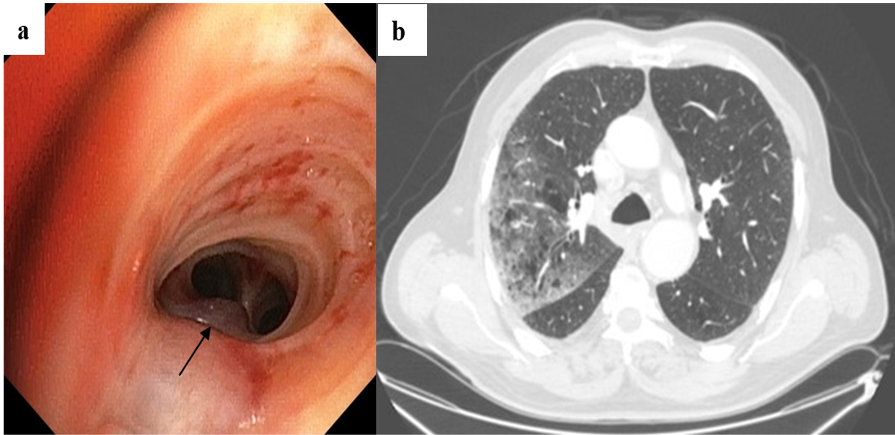

Diagnostic and therapeutic approach to endobronchial metastases from extra-thoracic neoplasms: A report of three cases and brief review of literature.

Soumaya Debiche, Houda Snene, Bochra Bouchabou, Monia Attia, Hana Blibech, Aïda Ayadi, Rym Ennaifer, Leila Ben Farhat, Nadia Mehiri, Bechir Louzir